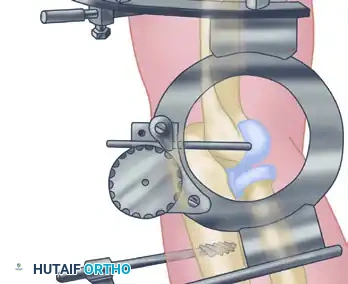

3. Ligament Reconstruction (The Arafiles Technique)

In cases of profound instability where dynamic fixation is unavailable or insufficient, surgeons may opt for ligament reconstruction with or without adjunctive fixation. The Arafiles technique utilizes a tendon graft routed through precisely drilled osseous tunnels to recreate the stabilizing vectors of the collateral ligaments.

The following sequence illustrates the complex reconstruction for an old posterior dislocation of the elbow, demonstrating the slot created in the trochlea and the specific lines of drill holes (A to D) that dictate the course of the tendon graft.

Note the intact forearm flexor origin during the completed repair, which provides secondary dynamic stability to the medial aspect of the reconstructed joint.